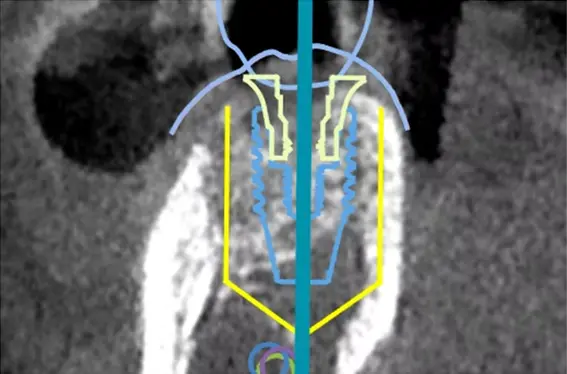

Xガイドは、歯や骨の状態に加え、神経や血管の位置を含めた3D画像を手術中にリアルタイムで表示し、インプラントの埋入位置と角度を正確にナビゲートするシステムです。

このシステムでは、CTスキャンデータをもとに事前シミュレーションを行い、手術中にその計画に沿って施術が進められます。GPS測定による位置情報と、光学技術を組み合わせることで高精度な処置が可能となり、重要な組織への配慮にもつながります。

ナビゲーションシステム(Xガイド)の画像